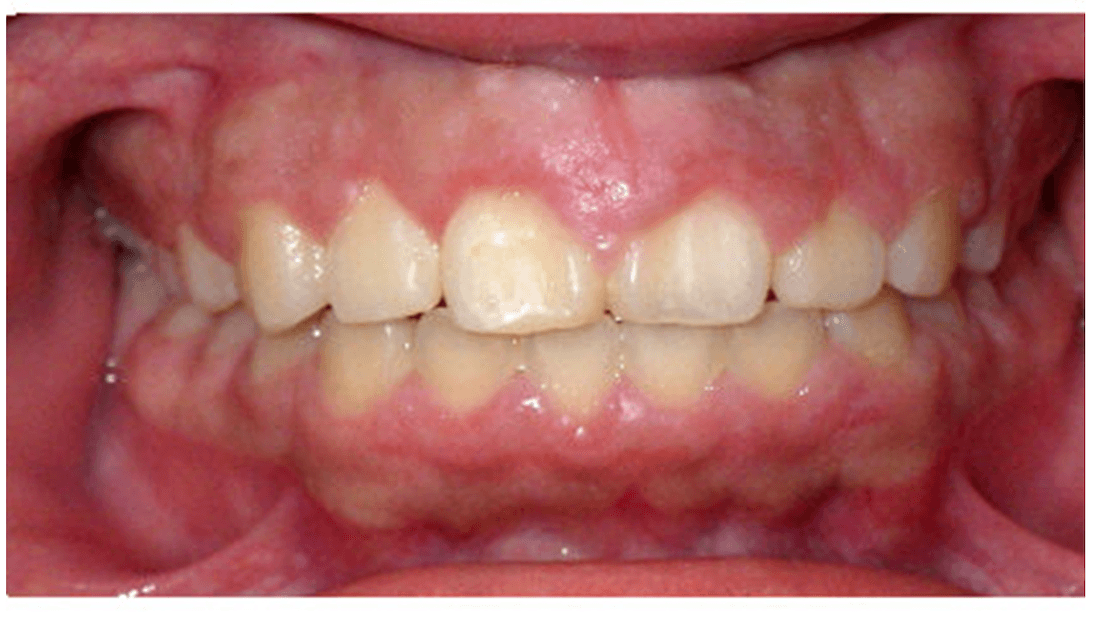

This patient presented with severe tooth misalignment, making it difficult for them to chew effectively. Our pediatric dentists corrected the situation with early orthodontic intervention using limited braces to address tooth alignment.

Early tooth correction sets the patient up for success for a second phase of tooth alignment with braces or clear aligners in the future.